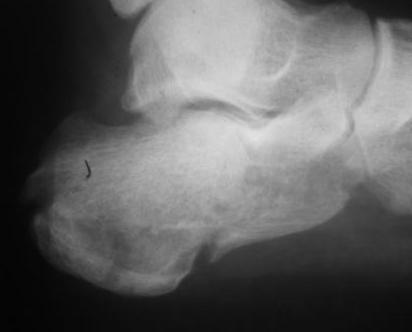

Re: перелом пяточной кости

послал Александр Кутков 06 Ноябрь 2010, 13:42

Из личного опыта, кстати после снятия кортикальной створки, репозицию удобно делать роторасширителем.